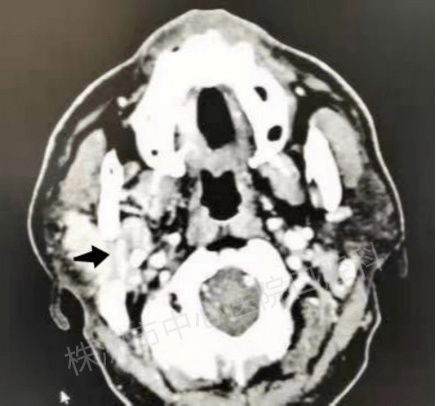

腮腺肿瘤的诊断

可通过详细询问病史,细致的临床检查,影像学检查(包括 B超、CT、MRI等),常可初步判断腮腺肿瘤的性质。 腮腺肿瘤术前一般不做活检,因为无论良、恶性肿瘤,均有发生瘤细胞种植的危险。 如想提高术前诊断准确率, 可考虑细针吸活检。 采用外径为0.6mm的细针头,吸取少量组织,涂片做细胞学检查,判断肿瘤良恶性。 但细针吸活检有其局限性,获取组织很少,少量组织的涂片难以概况肿瘤全貌,位置深的小肿瘤可能漏诊。 因此腮腺肿瘤的确切诊断常依赖于肿瘤全部切除后的石蜡切片诊断。 根据肿瘤的生物学行为,大致可将腮腺恶性肿瘤分为三类: 1.高度恶性肿瘤; 2.低度恶性肿瘤; 3.中度恶性肿瘤。